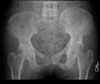

Masculino, 12 anos

Síndrome da sincondrose isquiopúbica assimétrica (Doença de Van Neck-Odelberg)

Variante da normalidade (em geral assintomático)

Crianças

Alargamento e radioluscência na sincondrose isquiopúbica, que simula neoplasias, infecção;